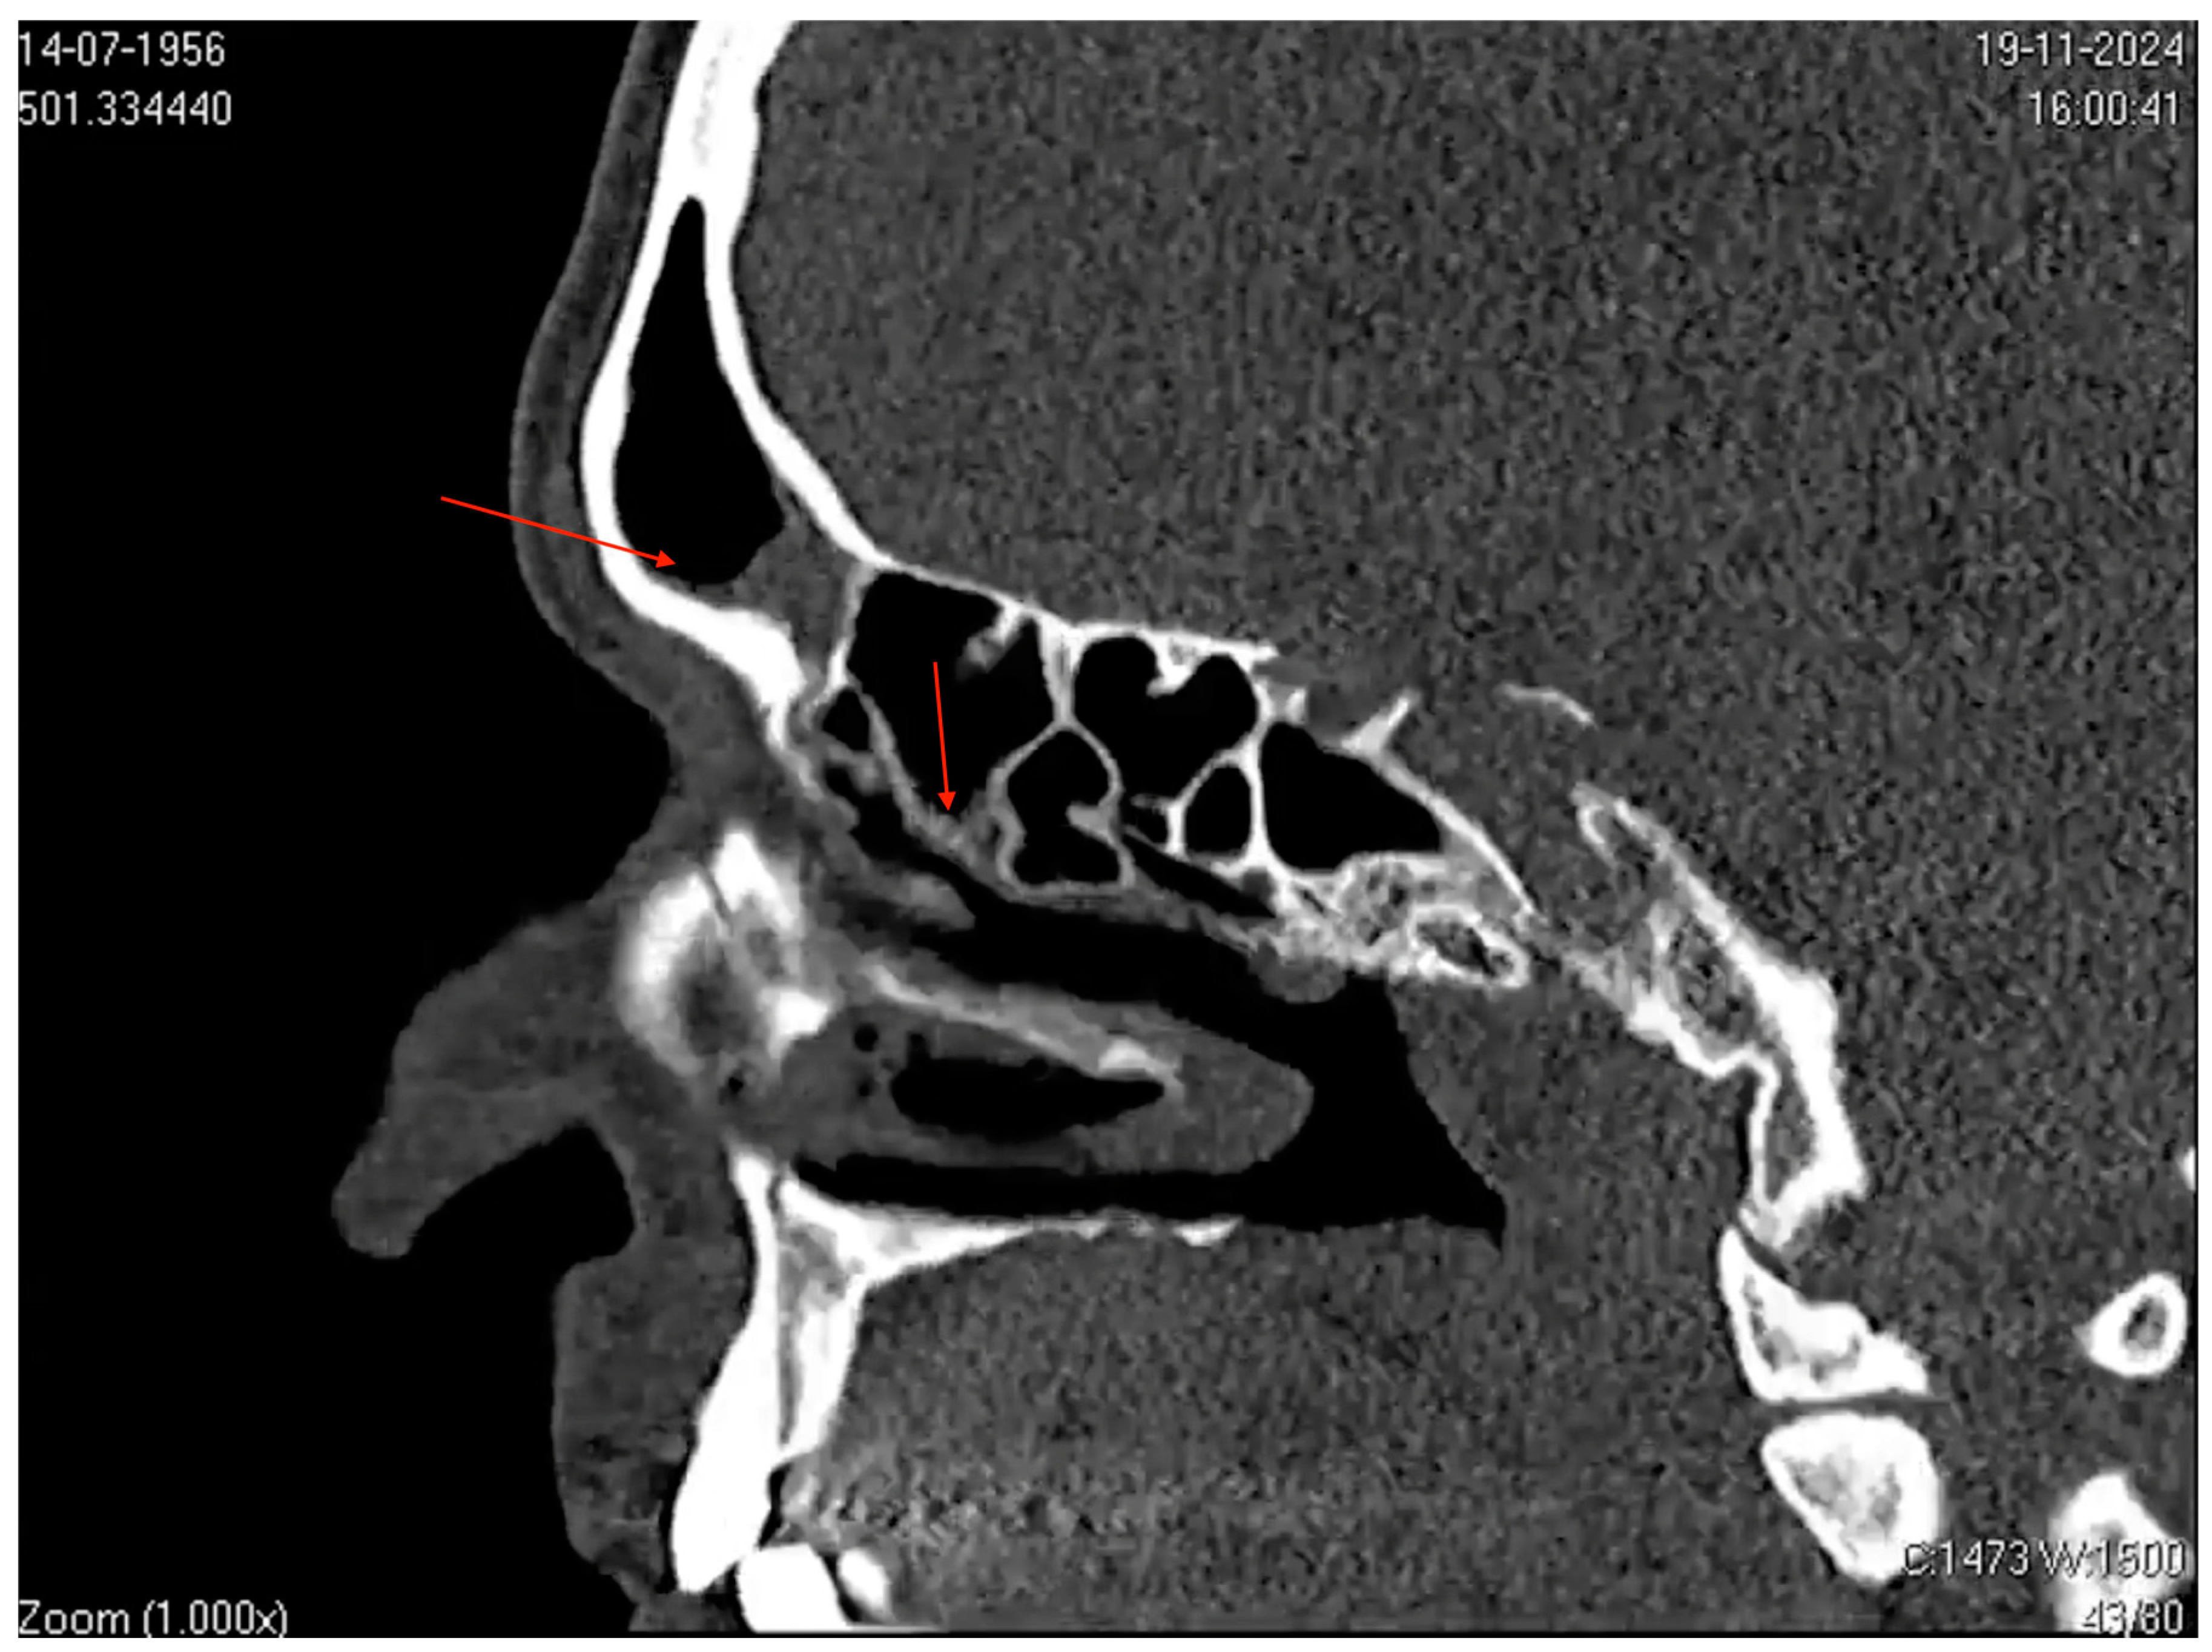

Additionally, CT scans of the paranasal sinuses showed mucosal thickening associated with secretions in the frontal sinuses and ethmoidal cells bilaterally, along with mild mucosal thickening in the maxillary sinuses, consistent with sinusitis (Figure 3). This presentation strongly suggests an underlying infection or an inflammatory process.

Figure 3.

Computed tomography (CT) image of the paranasal sinuses in the sagittal plane. The image shows mucosal thickening and partial opacification in the frontal sinus (highlighted by the superior red arrow) and ethmoid air cells (highlighted by the inferior red arrow). Narrowing of the sinus drainage pathways is also evident. These findings are consistent with those of acute and subacute sinusitis.